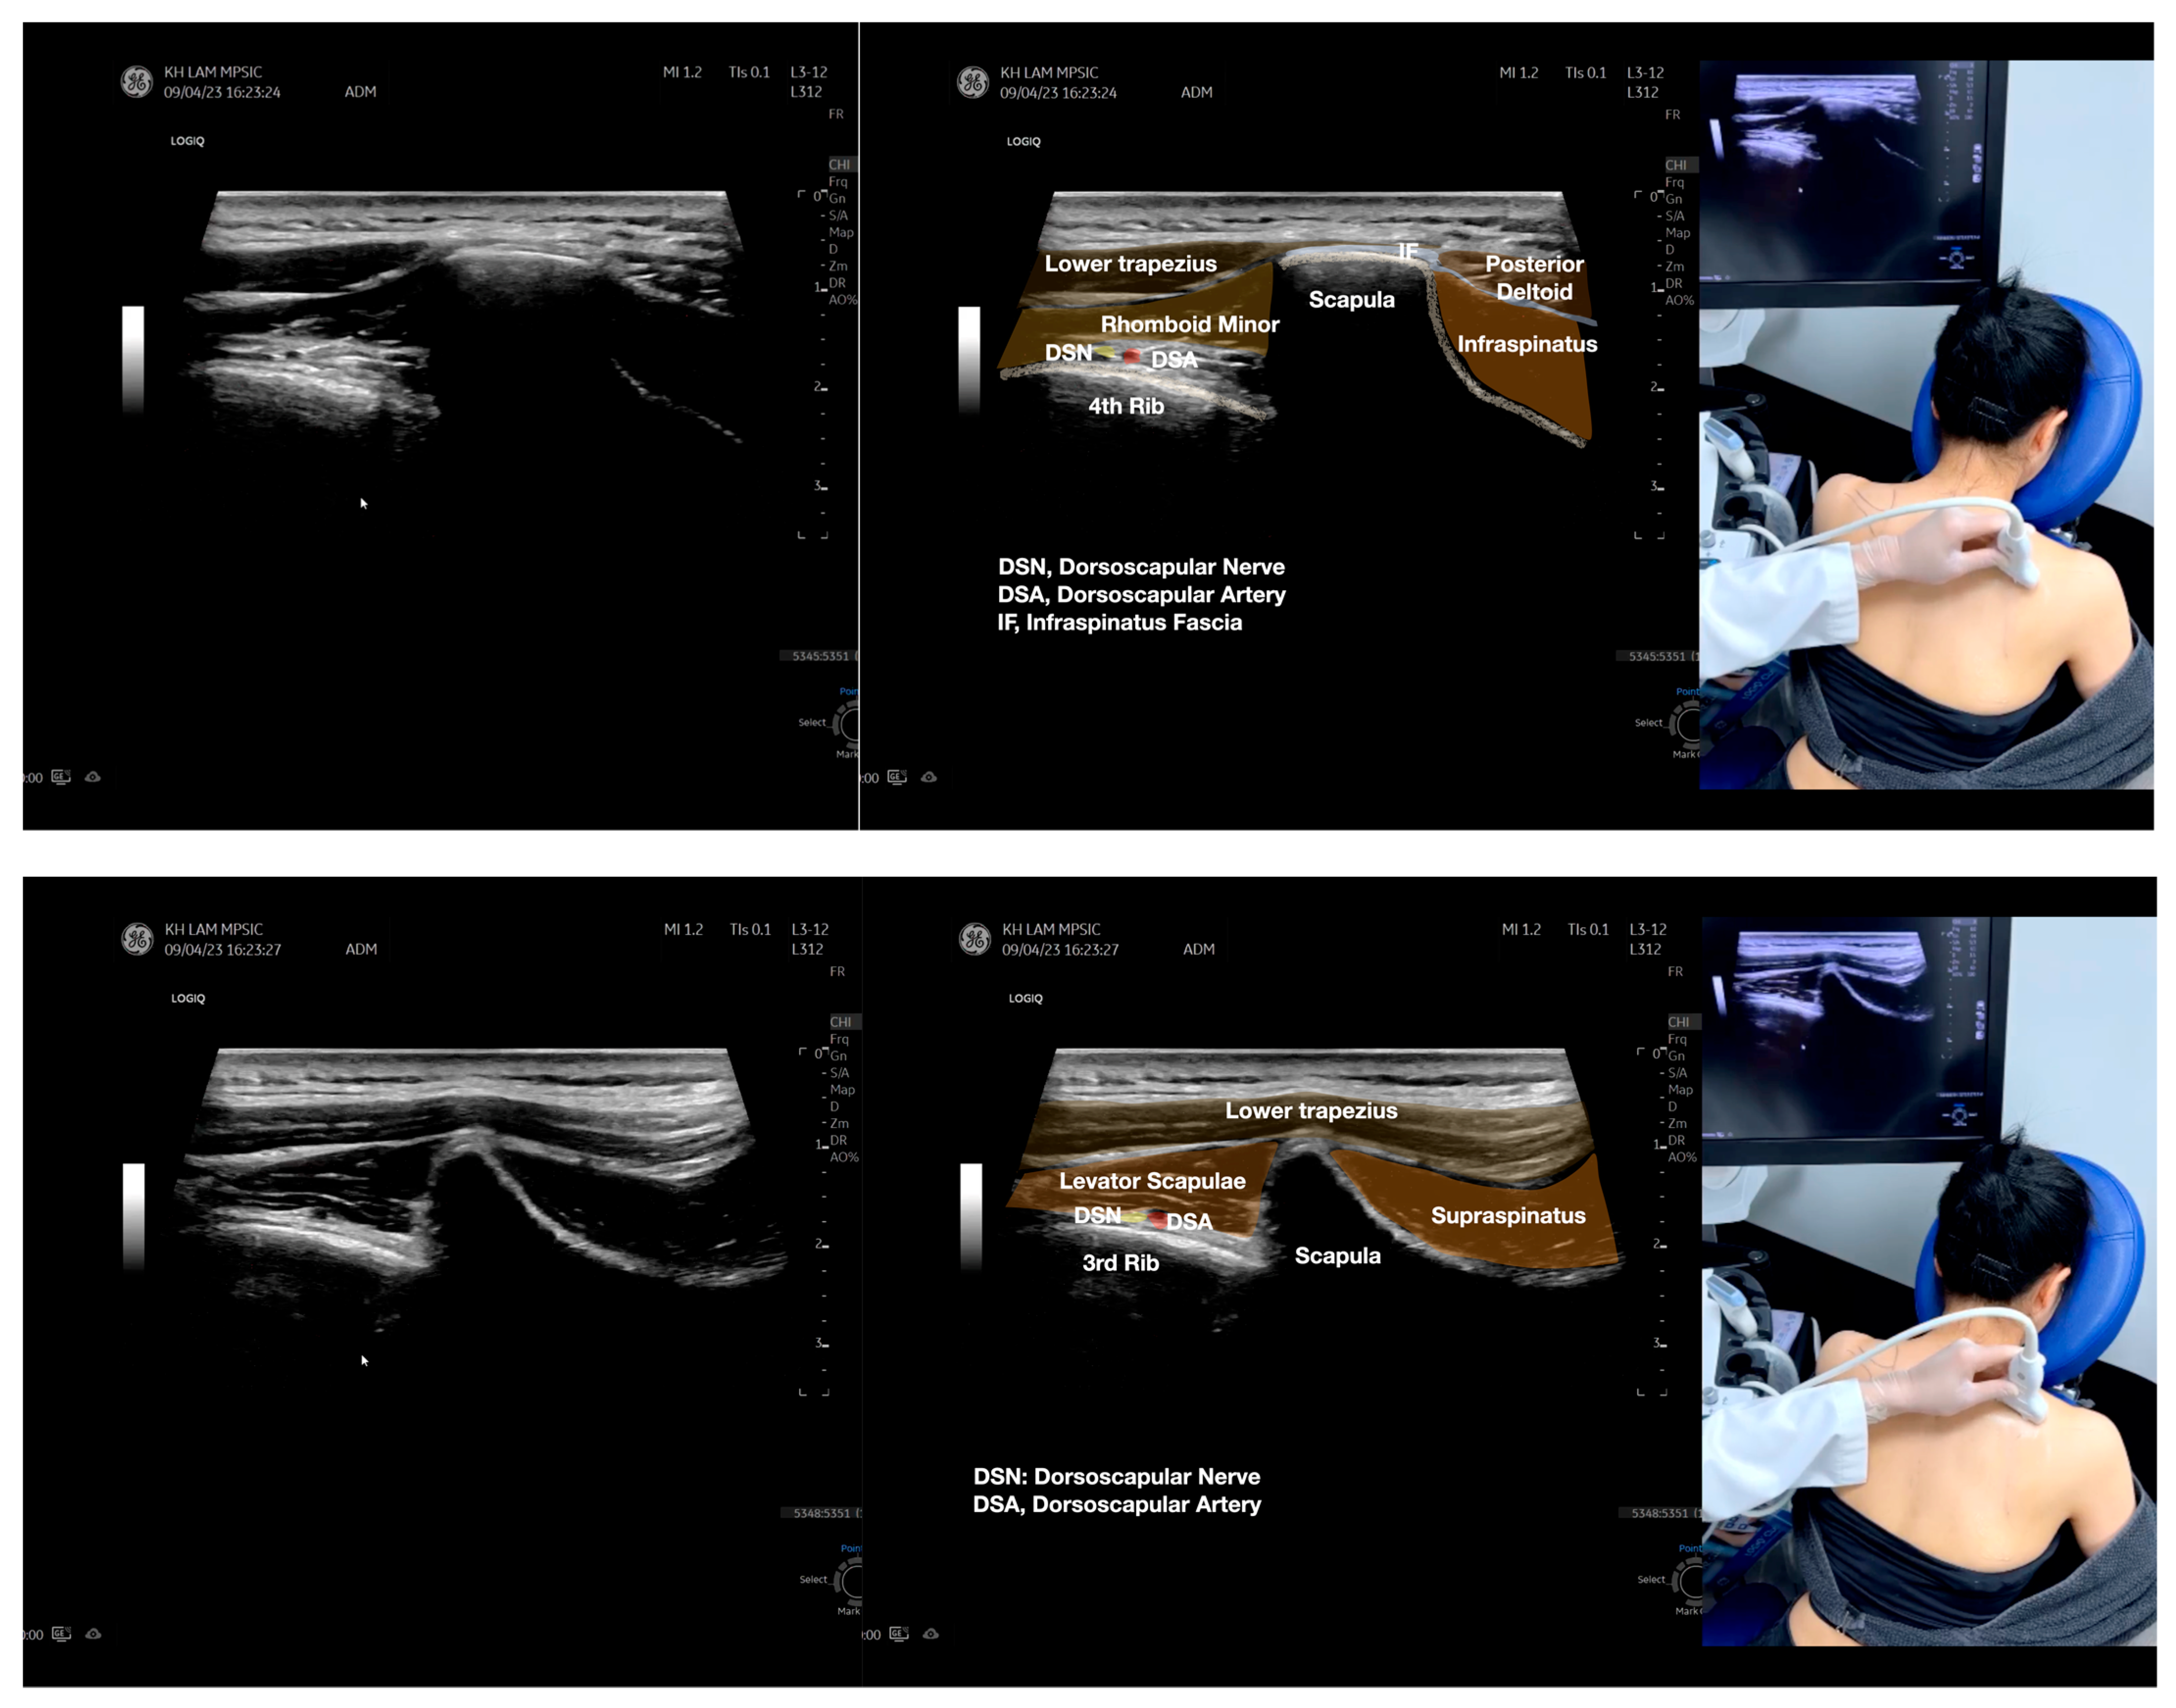

Figure 2.

Sonoanatomy of the lateral border of the inferior trapezius, its related muscles, and the infraspinatus fascia. The step-by-step scanning techniques of the structures illustrated in this figure have been shown in Video S6. Available online: https://www.dropbox.com/s/vjj49wiwdsidouz/Figure%202.docx?dl=0 (accessed on 1 January 2023). Dynamic ultrasound scanning of the anterior shoulder with the humerus externally rotated (palm up), elbow straight, and the shoulder actively flexed and abducted at about 90 to 100 degrees shows that the fibrotic and thickened bursa was noted to be snapping between the subscapularis tendon and the coracoacromial ligament, as shown in Video S3. The patient noticed this snapping during many of his daily activities with his shoulder flexed just above 90 degrees, e.g., taking off clothes and combing hair. Ultrasound-guided injection of the thickened and fibrotic bursa did not reproduce the usual pain nor reduce the pain, and it did not improve the shoulder snapping and flexion power with the elbow straight, shoulder flexed to 90°, and the humerus externally rotated (palm up). Ultrasound-guided injection of the cortical break reproduced the concordant pain and temporarily and partially reduced the pain with snapping and residual anterior shoulder pain (Video S4), but it did not change the snapping or weakness in the right shoulder flexion with the humerus in external rotation. With the failure of direct anterior treatment to the suspected lesions, it was essential to further explore other causes for the anterior painful snapping. Further detailed musculoskeletal examination of the scapular movement showed that the right scapulothoracic movements were not smooth compared to the left counterpart (Video S5) [4,5]. There might be some disruptions in the right infraspinatus fascia (IF) and its related muscles, including the lateral edge of the right inferior trapezius, rhomboid minor and major [6], teres major, latissimus dorsi [7,8] (LD), and posterior deltoid attachments to the IF [9,10]. Clinically, prominent and active trigger points were observed in the right infraspinatus muscle. Holding the inferior angle of the scapula, with the examiner’s fingers, especially over the origin of the teres major muscle over the scapula, the latissimus dorsi [11,12,13] and the scapular insertion of the rhomboid major muscle significantly improved the power of the resisted shoulder flexion with the elbow straight and the shoulder flexed to 90° with the humerus externally rotated (palm up). In order to illustrate the utilization of ultrasound-guided sonopalpation and ultrasound-guided digital palpation for detecting the suspected lesions of the IF and its related muscles, we presented the following videos (Videos S6–S9) and still images (Figure 2, Figure 3, Figure 4 and Figure 5) to demonstrate the essential techniques and crucial points of getting the normal sonoanatomy of the IF and its related structures. The gross anatomy of the IF and its related muscles were also shown in Figure 6, Figure 7 and Figure 8.